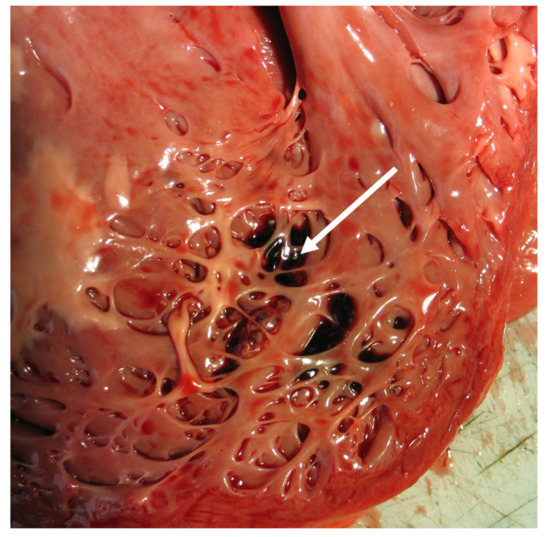

- Burke, A.; Mont, E.; Kutys, R.; Virmani, R. Left ventricular noncompaction: A pathological study of 14 cases. Hum. Pathol. 2005, 36, 403–411. [Google Scholar] [CrossRef] [PubMed]